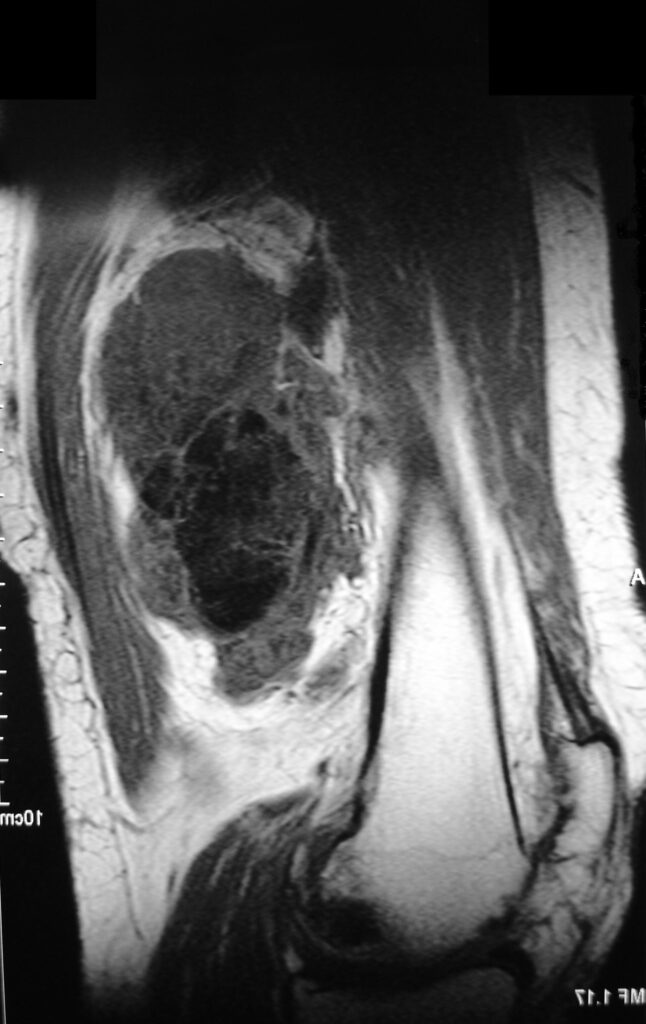

On radiographs, extraskeletal osteosarcomas show a mass with soft tissue density and variable amounts of mineralization best visualize on an Xray or CT scan, which may appear as a dense, cloudlike area (Fig. 1-3). A well circumscribe heterogeneous mass, Isointense to muscle on T1-weighted images and isointense to mildly hyperintense on T2-weighted images (Fig. 4-7). Mineralized areas will be dark on T1 and T2 weighted images.

Fig. 4 & 5: MRI of an Extraskeletal Osteosarcoma Axial (Fig. 4) and sagital (Fig. 5) T1-weighted MR image of an extraskeletal osteosarcoma demonstrates an isointense signal with muscle in the posterior compartment of the thigh. Neurovascular structures seem to be invaded by tumor.